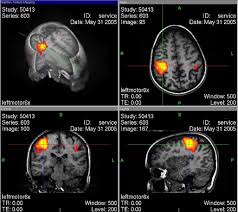

Adicionalmente aos resultados de fMRT(ressonância magnética funcional) e de PECT, investigações também encontraram mudanças nos padrões de EEG (eletroencefalograma) durante o transe. Infelizmente, os resultados nem sempre correspondem, o que pode ser explicado pelo grande número de diferentes configurações.